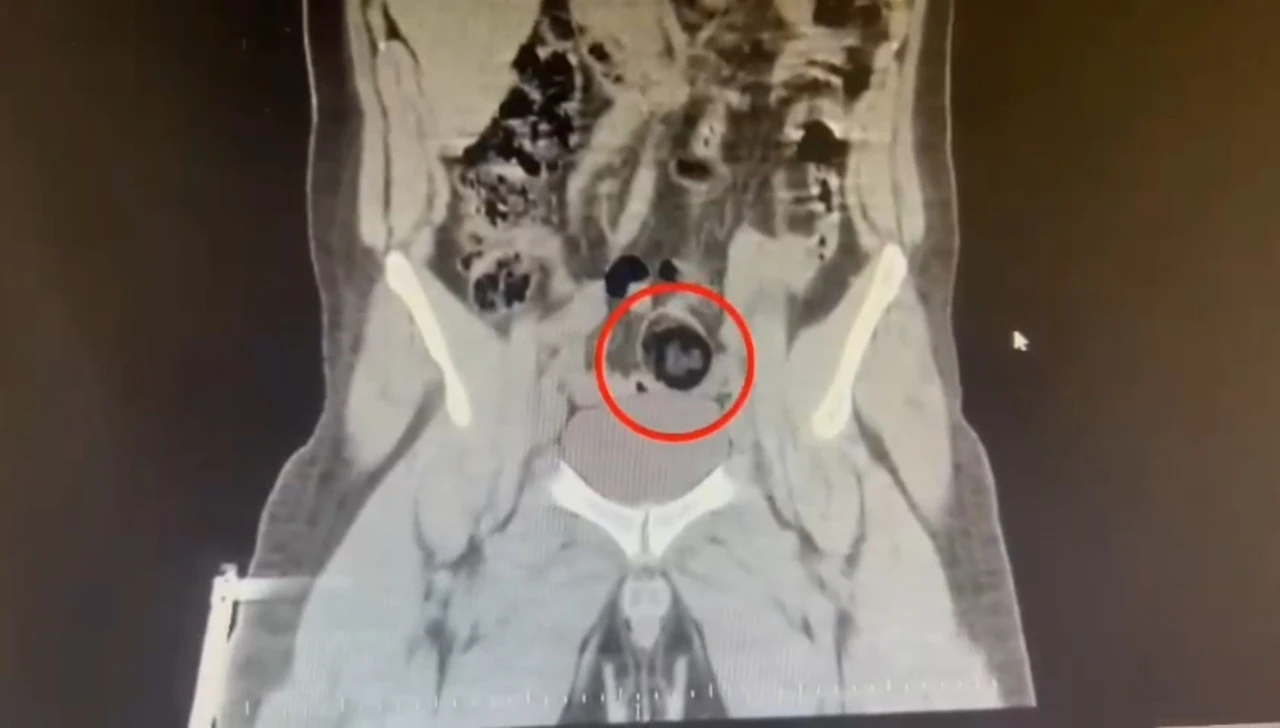

Kars Emniyet Müdürlüğü Narkotik Suçlarla Mücadele Şube Müdürlüğünce, savcılık koordinesinde kent merkezinde uluslararası uyuşturucu madde ticareti yapan kurye şahıslara yönelik operasyon düzenlendi. Bu kapsamda narkotik ekiplerince durdurulan yolcu otobüsünde İranlı kurye yakalanarak gözaltına alındı. Şüpheli hareketler sergilen kurye götürüldüğü hastanede yapılan iç beden muayenesinde makatında cisim olduğu anlaşıldı. Kuryenin makatındaki 105,98 gram metamfetamin gerçekleştirilen cerrahi müdahaleyle çıkarıldı. Gözaltına alınarak emniyete getirilen kurye, çıkarıldığı mahkemece "TCK-188 uyuşturucu veya uyarıcı madde imal ve ticareti yapmak" suçundan tutuklanarak cezaevine gönderildi.